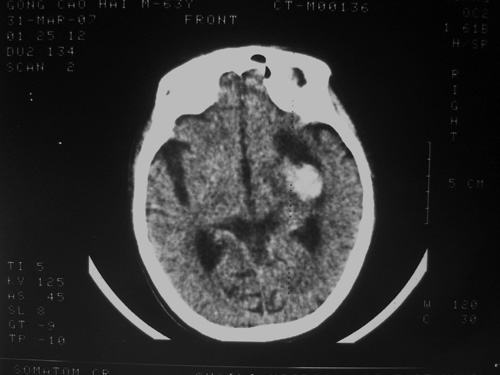

患者63岁,男。左侧肢体活动不灵一小时来诊。bp:175/75;家人否定有脑出血、脑梗死及其他病史。有嗜酒习惯。ct:右侧外囊区见不规则高密度影,边清,肯定是出血。可其周围低密度,边清,ct值与脑脊液相近,不像是水肿影,好似一软化灶形成。这种混合型病灶少见,请老师给予指导一下。

高密度灶为新鲜出血,临近低密度区为软化灶,可能为陈旧性梗塞或出血致。

软化灶出血,左侧脑室轻度受压。

双侧额岛叶萎缩,病者有嗜酒习惯,考虑可能由酒精中毒引起的脑软化灶,合并脑出血,右基底节区亦有软化灶